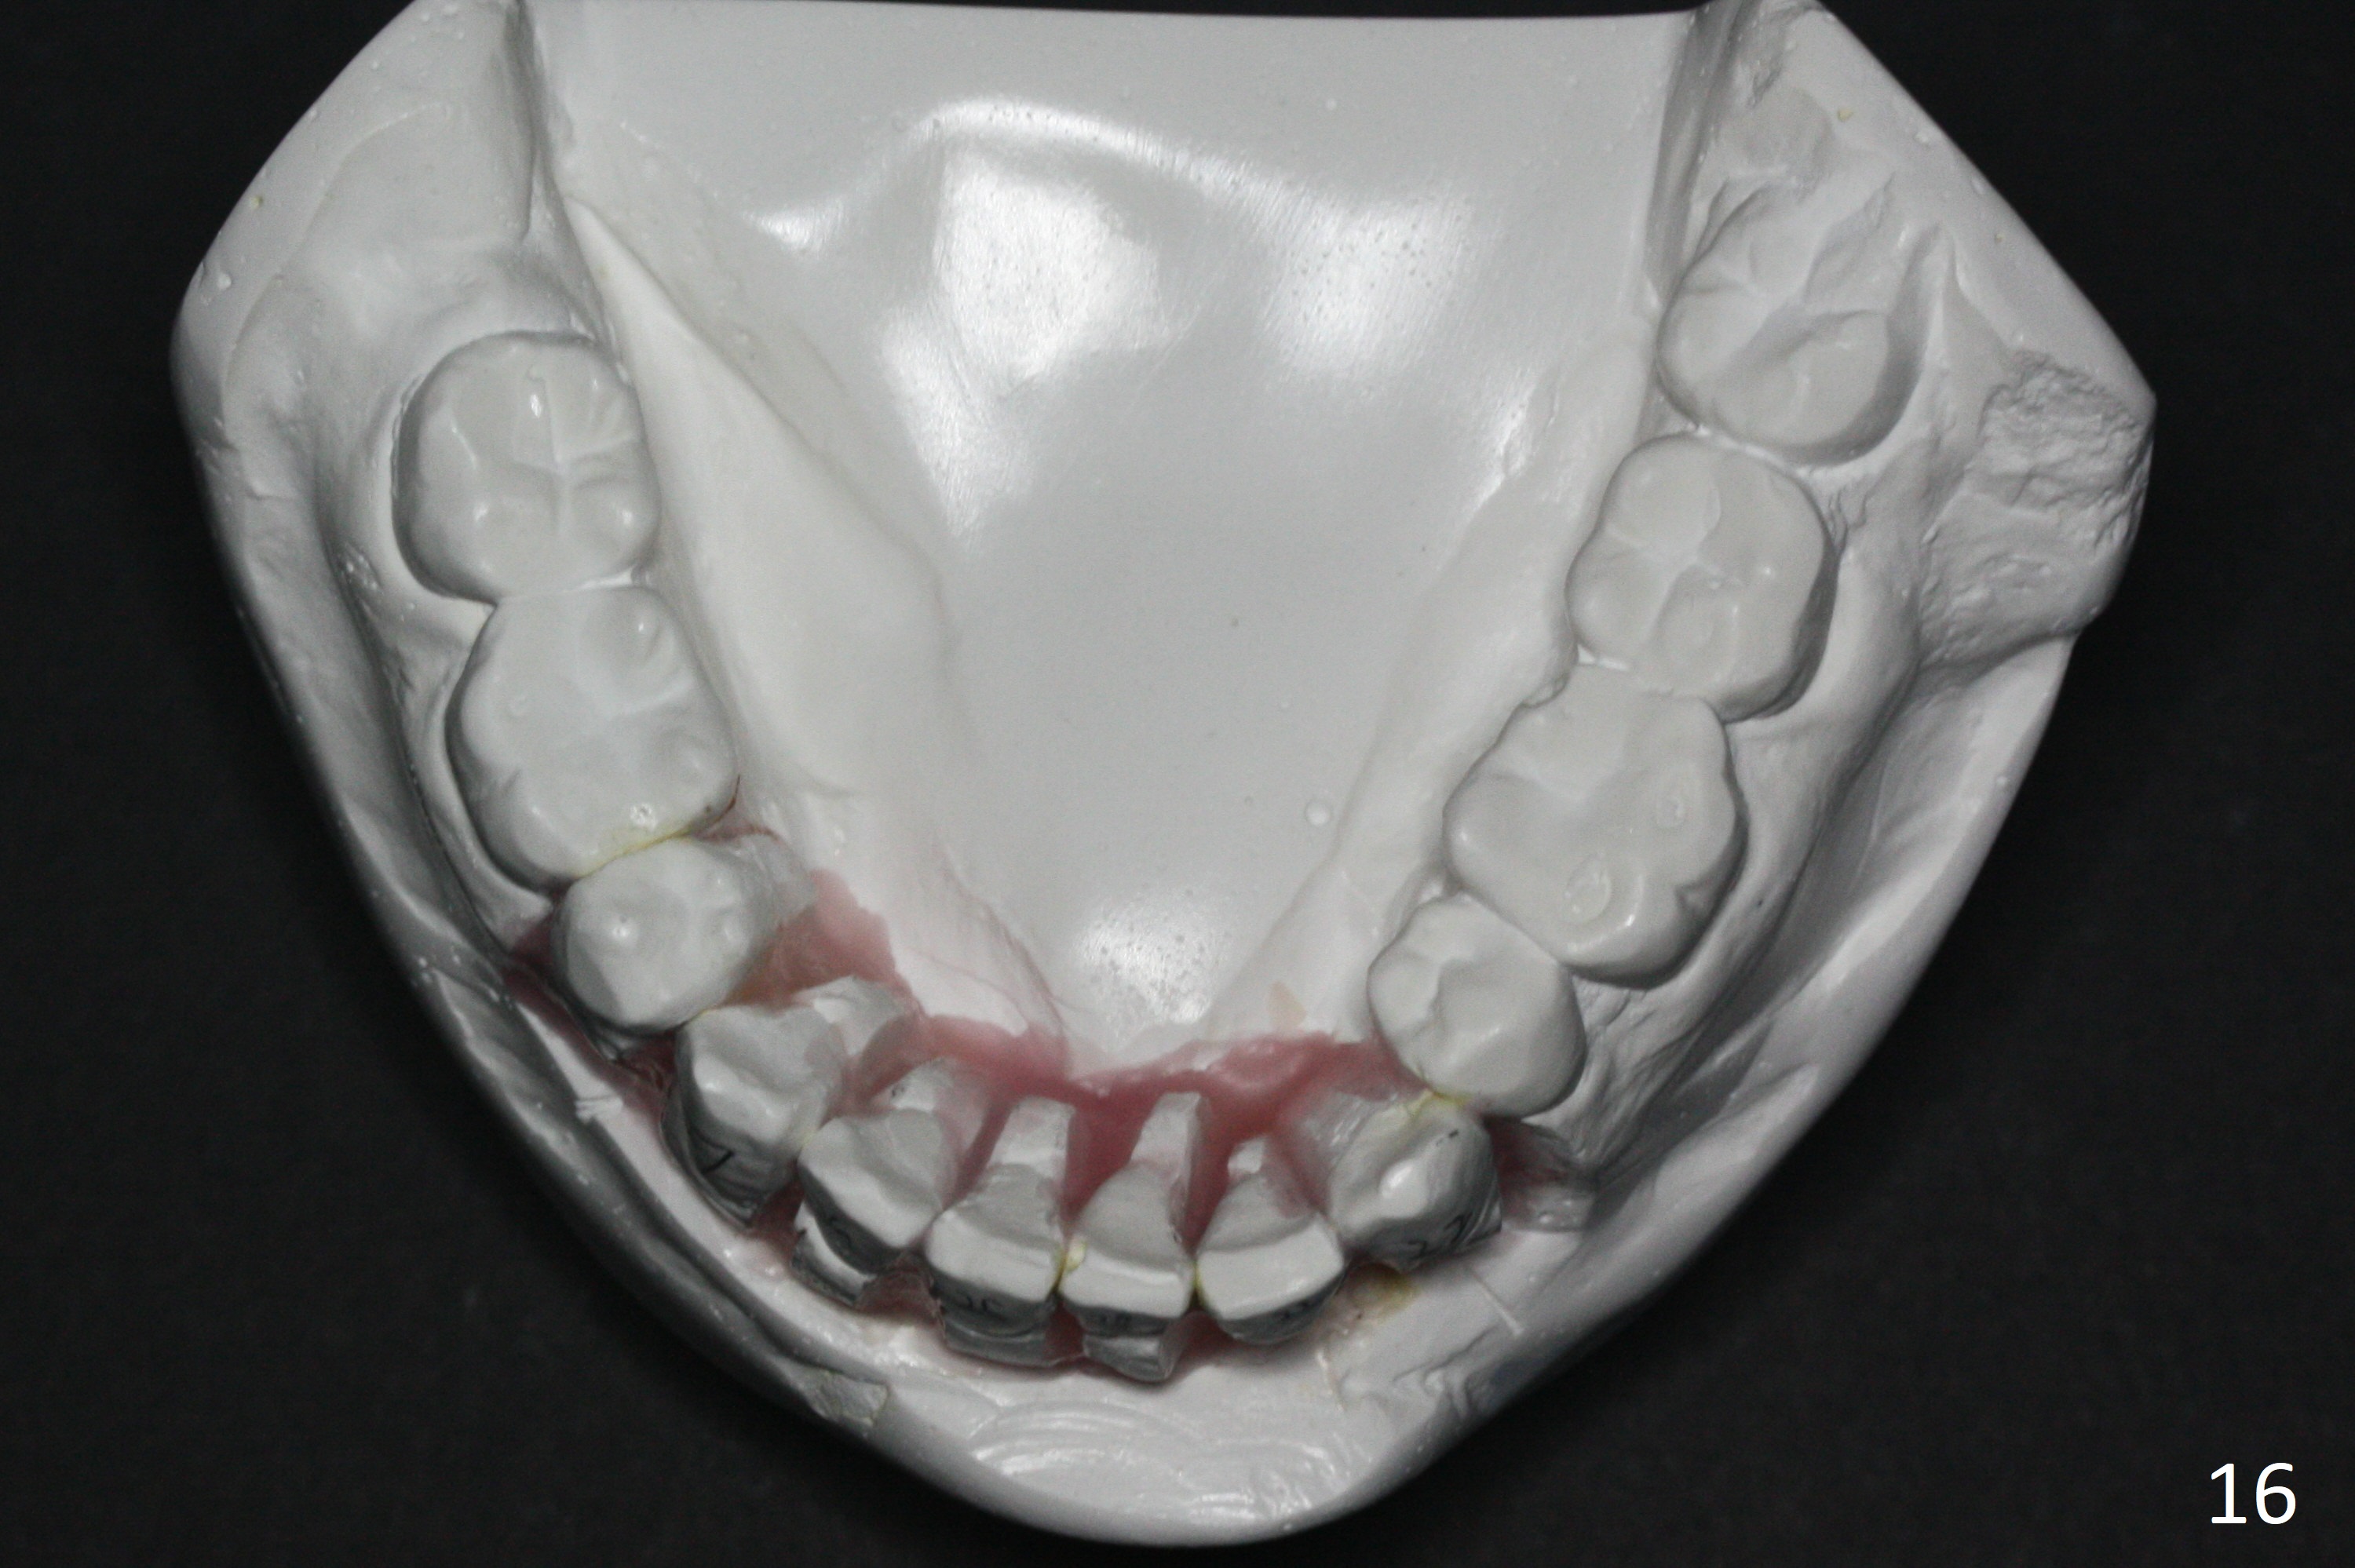

Enough Space For Crowding After Extraction? A 47-year-old man requests orthodontic treatment following SRP in other office (Fig.1-11). For severe crowding and midline shifting, extraction of four of the 1st bicuspids is imminent. Is it enough? To answer the question, model surgery is performed (Fig.12-16). 1st visit: periodontal maintenance, orthodontic consent (emphasizing oral hygiene) extract 4s and possibly L8s and separators. The beauty of this vist is that after local anesthesia and extraction including L8s, it is painless and easy to remove calculus from the proximal surfaces of the neighboring teeth. It is much easier to place separators after extraction. It is expected that there is no gingival erythema when the patient returns for bracketing. Take photos of UR3, similar to Fig.3. Molar banding is also anticipated to be easy with separator placement after extraction. Return to Ortho Cases Xin Wei, DDS, PhD, MS 1st edition 11/23/2017, last revision 04/28/2019